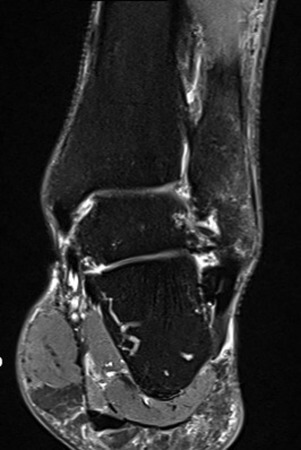

Anamnese: Die Patientin stellte sich zunächst mit Schmerzen im Bereich des linken OSG vor, nachdem sie auf Grund sehr eisiger Verhältnisse im Januar mit Grödel über 10 km gelaufen sei. Zudem habe sie eine Schwellung im Bereich der distalen Fibula bemerkt. Medikamente wurden nicht eingenommen, Vorerkrankungen waren keine bekannt. Bei der körperlichen Untersuchung bestand deutliche Druckdolenz und klar lokalisierbarer Klopfschmerz im Bereich der distalen Fibula dia-metaphysär linksseitig sowie eine Schwellung des OSG mit im Seitenvergleich ca. 2 cm Umfangsvermehrung an der Fibulaspitze. Das OSG sowie USG zeigte sich stabil, ein Talusvorschub bestand nicht. Die Rückfußposition war regelrecht, die Rückfußsehnen ohne Funktionseinschränkung. Eine deutliche Einschränkung bestand in der Dorsalextension sowie in der Eversion. Sonografisch zeigte sich eine subperiostale Schwellung als mögliches Zeichen eines Hämatoms mit fraglicher Unterbrechung des Periosts. Zur weiteren Abklärung erfolgte eine MRT des linken OSG. Dieses ergab eine frische Stressfraktur der distalen Fibula im Bereich der distalen Diaphyse und Metaphyse ohne Nachweis einer Dislokation mit periossärer Weichteilödematisierung (Grad IV nach Arendt und Griffiths) (vgl. Abb. 1Abb. 2).

Vor der Behandlung zeigte der AOFAS Score 40 Punkte, nach drei Behandlungen lag der Score bei 70 und nach fünf Behandlungen ermittelten wir einen Wert von 100. Somit war der Wert eines gesunden Sprunggelenkes erreicht. Zur Ermittlung der Schwellung haben wir den Umfang an der Fibulaspitze im Seitenvergleich gemessen, der vor der Behandlung an der frakturierten Fibula um ca. 10% größer war als auf der Gegenseite. Nach den ersten drei Behandlungen waren die Umfänge im gleichen Bereich identisch. Die anfänglich deutlich limitierte Dorsalextension sowie Hebung des Fußaußenrandes des betroffenen Sprunggelenkes war nach der gesamten Therapie wieder seitengleich normwertig. Der anfänglich intensive Klopfschmerz wurde bereits nach der zweiten Behandlung nicht mehr angegeben. Auch das alltägliche Schmerzlevel verringerte sich nach jeder Behandlung deutlich, sodass bereits nach drei Behandlungen mittels ESWT sowohl mit als auch ohne Orthese kaum noch Schmerzen vorhanden waren und bereits eine Schrittzahl von ca 10.000 am Tag möglich war. Radfahren war ab der 3. Behandlungswoche erlaubt und der Patientin beschwerdefrei möglich. Nach drei Behandlungen (ab der 4. Woche) wurde bereits von der Stabilorthese auf den elastischen Anteil reduziert. Im Rahmen der Trainingstherapie wurden ab der 4. Wochen schon kurze Läufe (10- 15 Min.) auf dem Laufband begonnen, die ebenfalls beschwerdefrei toleriert wurden. Am Ende der Behandlung legte die Patientin bereits 15.000 Schritte am Tag zurück. Ein zwischenzeitlich durchgeführtes Kontroll-Röntgenbild zeigte keine sekundäre Dislokation. Die sechs Wochen nach Beginn der Therapie durchgeführte MRT zeigte eine nahezu vollständige Konsolidierung des Knochens (vgl. Abb. 3 und Abb. 4).